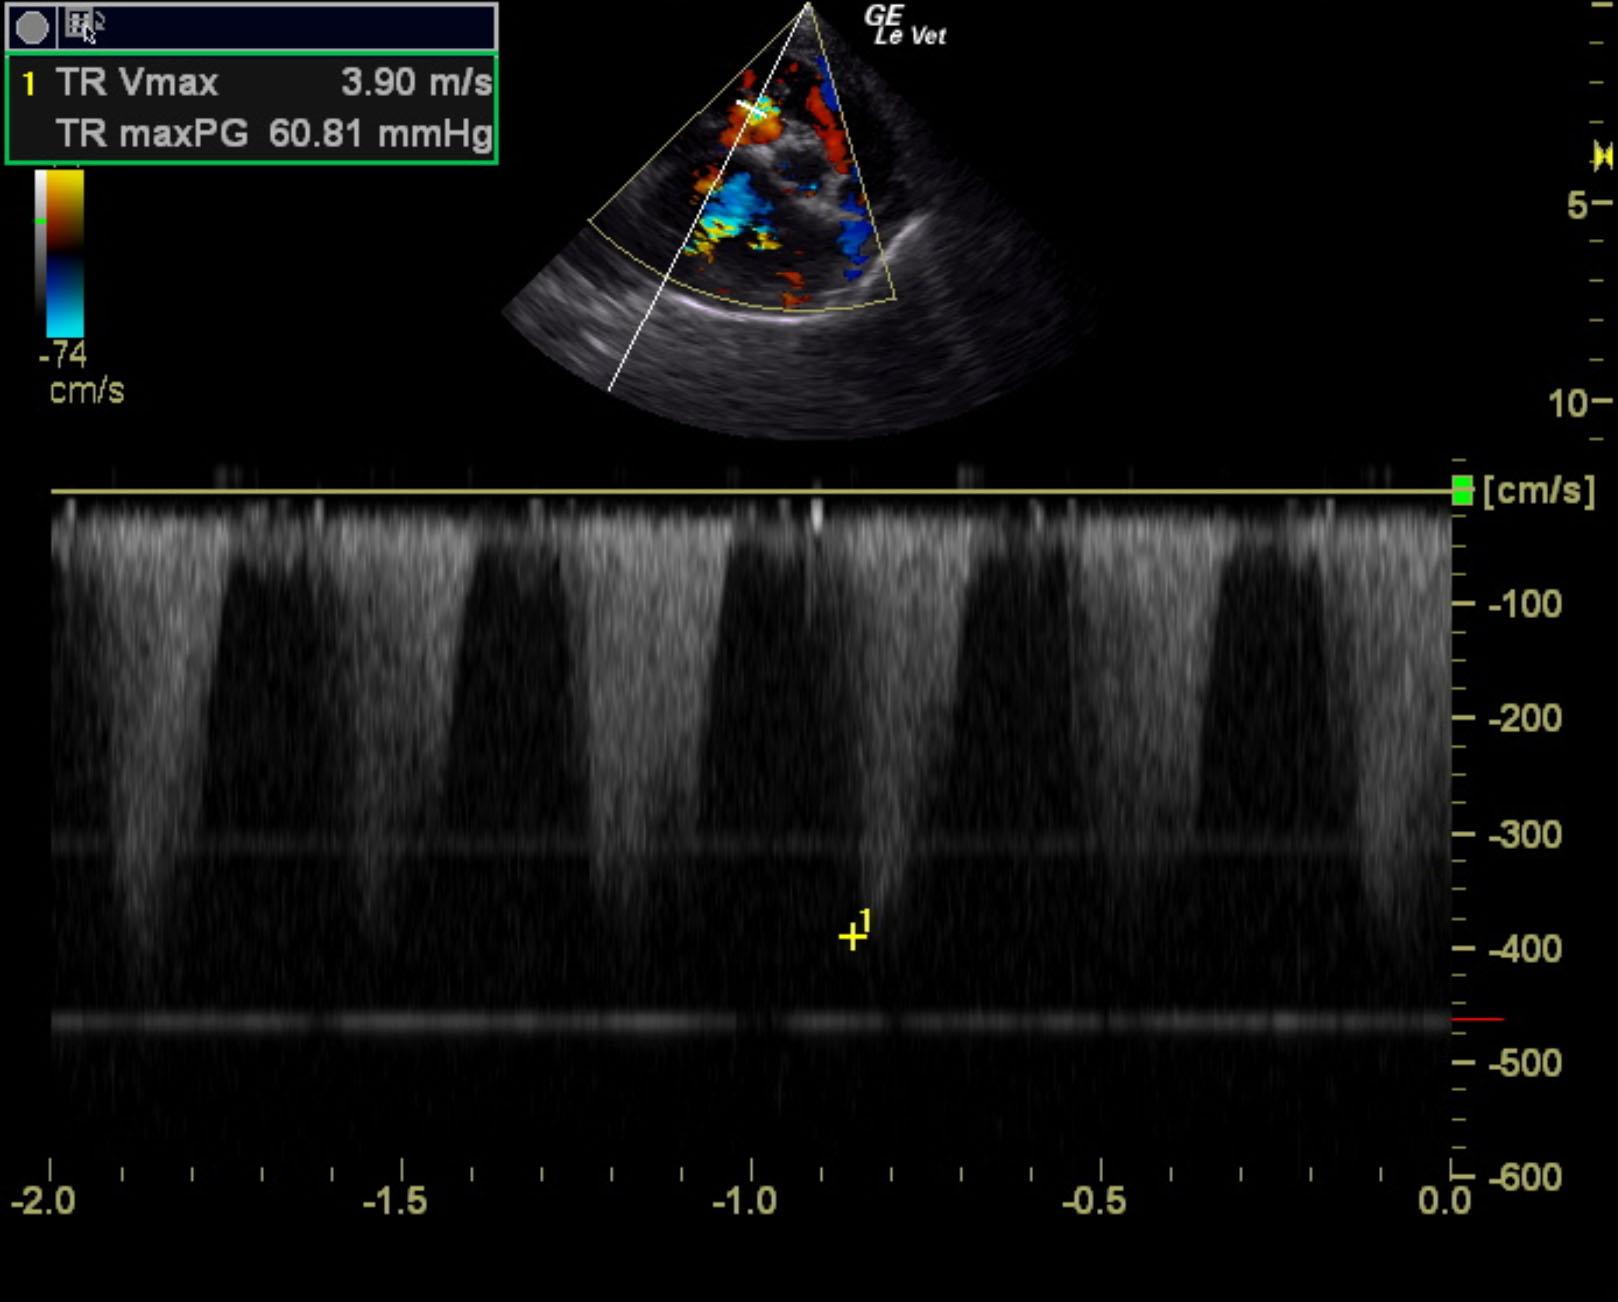

The cardiac presentation revealed moderate left and right sided overload with tricuspid and mitral valve vegetative lesions. Left atrial and right atrial enlargement was noted. Right ventricular overload was noted with flattening of the ventricular septum. Slight prolapse of the anterior mitral valve leaflet was noted. Prolapse of the tricuspid vavle was also noted. Significant pulmonic insufficiency and tricuspid insufficiency was noted. This is consistent with pulmonary hypertension.

Tricuspid insufficiency velocity 3.9 m/sec